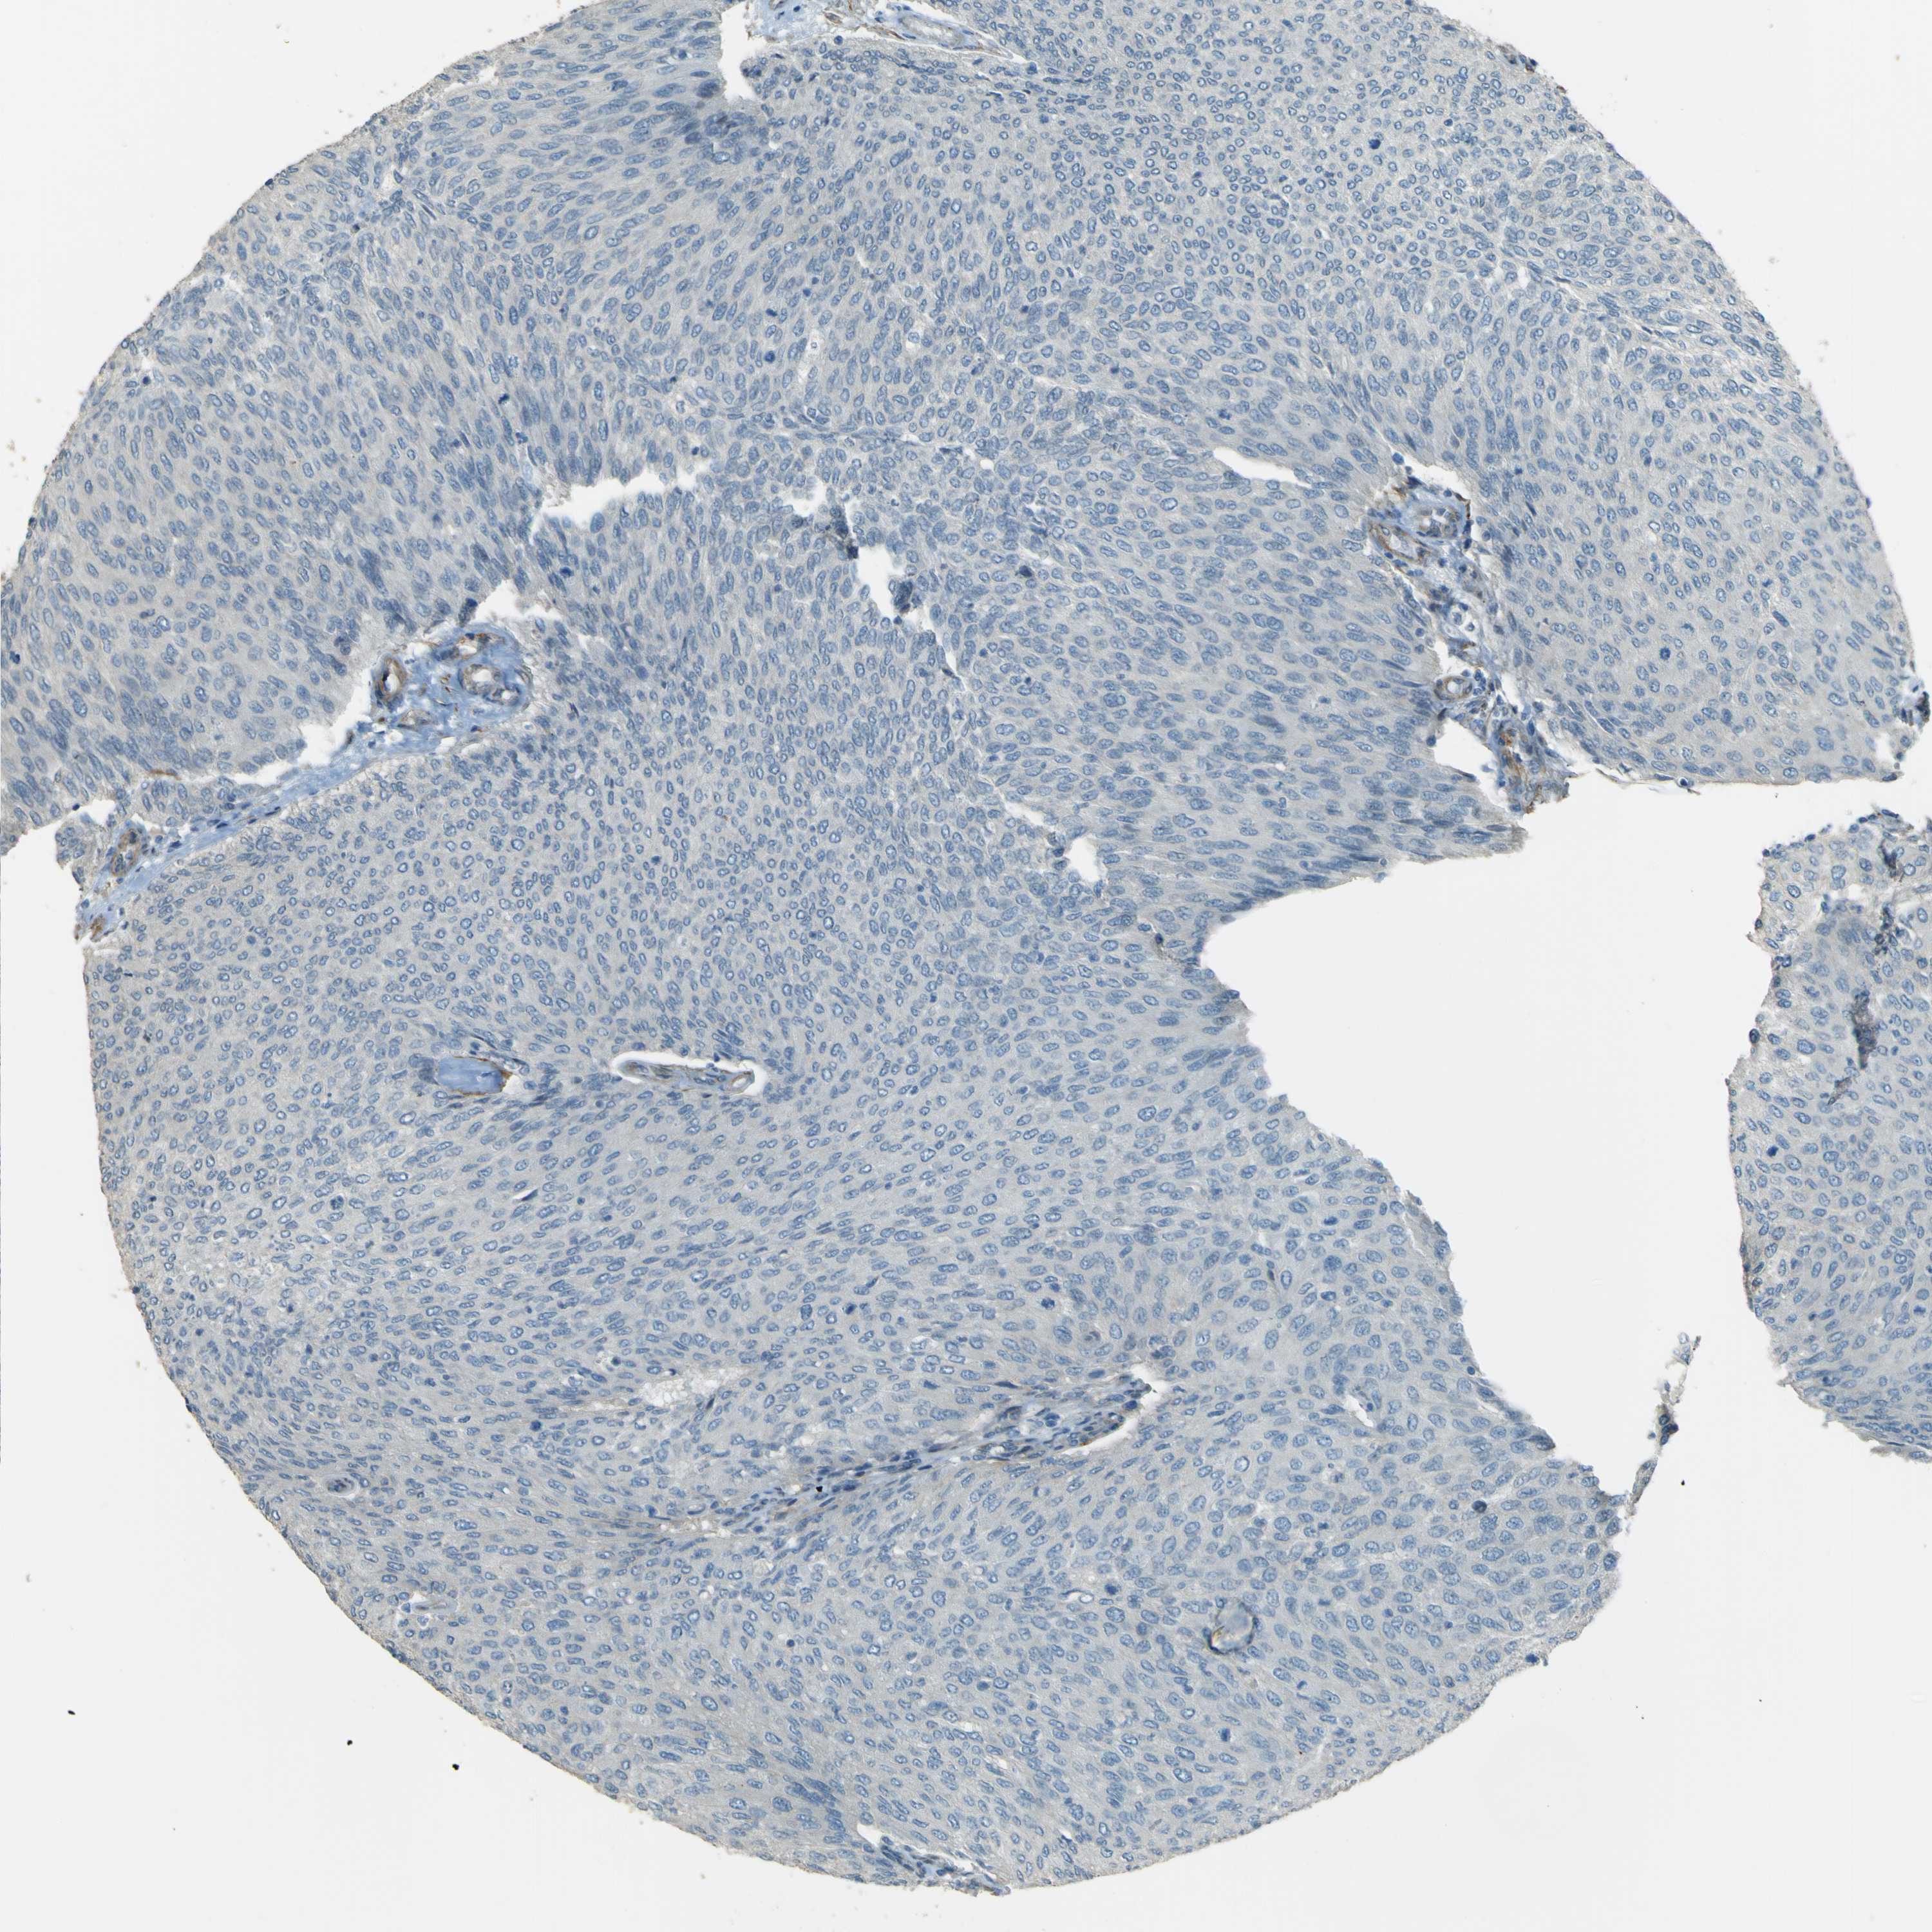

UROTHELIAL CANCER - Protein expressioni

A mouse-over function shows sample information and annotation data. Click on an image to view it in a full screen mode. Samples can be filtered based on level of antibody staining by selecting one or several of the following categories: high, medium, low and not detected. The assay and annotation is described here.

Note that samples used for immunohistochemistry by the Human Protein Atlas do not correspond to samples in the TCGA dataset.

Antibody stainingi

Antibody staining in the annotated cell types in the current human tissue is reported as not detected, low, medium, or high, based on conventional immunohistochemistry profiling in selected tissues. This score is based on the combination of the staining intensity and fraction of stained cells.

Each image is clickable and will lead to virtual microscopy that enables deeper exploration of all samples and also displays staining intensity scores, fraction scores and subcellular localization as well as patient and tissue information for each sample.

Antibody HPA011185

Urothelial carcinoma, Low grade

Urothelial carcinoma, High grade